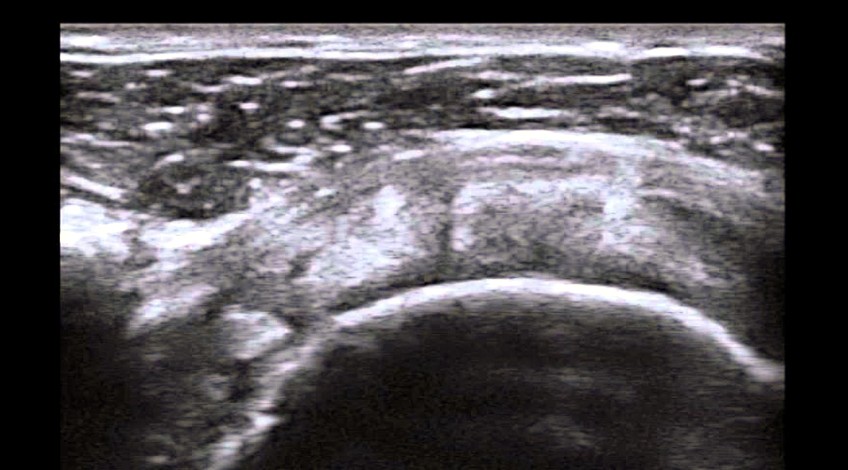

- ¿Qué es? Es un examen que estudia las articulaciones de miembros superiores o inferiores o regiones musculares, por ejemplo: tobillo, pies, manos, codos, hombros. Se indica realizarlo frecuentemente por: esguinces, tendinitis manguito rotador, rotura del manguito rotador, síndrome del túnel carpiano, epicondilitis, codo del tenista, codo del golfista, desgarros musculares, tendinitis rotuliana, tenosinovitis de Quervain, etc